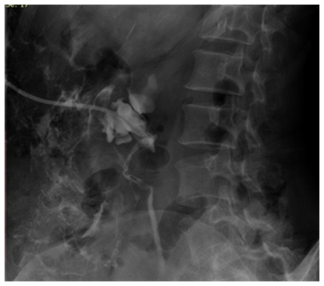

Major complication occurred in 4.33% (3 of 69 units), gross haematuria being most common 2.89% cases. Inferior vena cava injury was a rare serious complication encountered in one patient (1.44%), and occurred during tract dilatation. Haematuria continued for 36hours after PCN and the patient died of acute renal shut down (Figure 3). Minor complication rate was 50.72% with persistent pain at PCN site (17.39%) being the most common. On excluding pain, minor complication rate was 33.33%.

Figure 3 Post PCN nephrostogram showing perinephric extravasation of contrast a complication of the procedure.